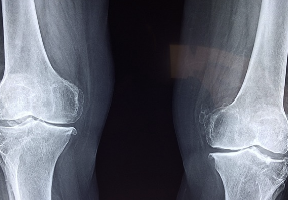

콘드로이친 효능 및 부작용 등 콘드로이친과 관련된 정보 알아보도록 하겠습니다.콘드로이친(Chondroitin)은 연골 조직과 결합되어 있는 큰 분자인 그리코사미노글리칸의 일종입니다. 연골 조직을 형성하는 세포들이 만들어내며, 연골의 탄성과 내구성을 유지하고 연골 조직의 재생과 보호를 돕는 역할을 합니다. 또한 염증 억제 효과가 있어 관절염 등의 염증성 관절질환의 치료에도 사용됩니다.

- 연골 보호: 콘드로이친은 연골 조직의 재생과 보호를 돕는 역할을 합니다. 연골 조직은 연령이 들면서 파괴되는 경향이 있으며, 적절한 콘드로이친 섭취는 연골 조직의 파괴를 줄여주어 건강한 연골 조직을 유지하는 데 도움을 줍니다.

- 관절 염증 억제: 콘드로이친은 염증 억제 효과가 있어, 관절염 등의 염증성 관절질환의 치료에 효과적입니다.

- 관절 윤활: 콘드로이친은 관절 내 윤활제 역할을 하여 관절 부위의 마찰을 감소시켜 관절 통증을 완화시키고, 관절의 움직임을 개선시킵니다.

- 연골 탄성 향상: 콘드로이친은 연골 조직의 탄성과 내구성을 증가시켜 관절 내부의 충격을 완화시켜 줍니다.